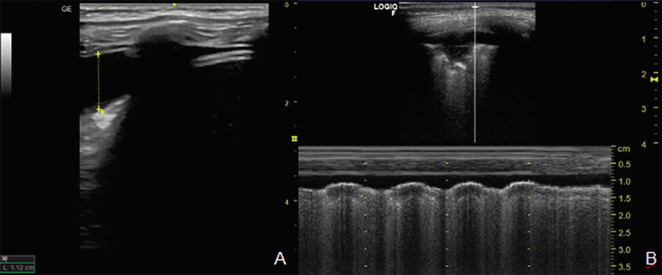

• En modo M: este movimiento genera la imagen de la “orilla del mar” (“seashore sign”), donde la zona superior (pared torácica inmóvil) presenta un patrón de líneas paralelas horizontales “olas”, y la inferior (pulmón ventilado/móvil) un aspecto granular “arena”, que confirma la presencia de aireación normal (Fig. 6).

Figura 6. Imagen de la orilla del mar.